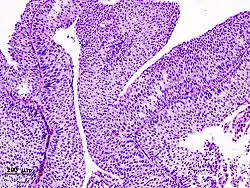

The 1973 WHO grading system for transitional cell carcinomas (papilloma, G1, G2 or G3) is most commonly used despite being superseded by the 2004 WHO[14] grading for papillary types (papillary neoplasm of low malignant potential [PNLMP], low grade, and high grade papillary carcinoma). High-grade carcinoma typically displays more pleomorphism, multiple mitoses, euchromatin and relatively prominent nucleoli, and uneven distribution of nuclei.

Transitional cell carcinoma, being low-grade to the left, and high-grade to the right. H&E stain -

Papillary transitional cell carcinoma, low grade -